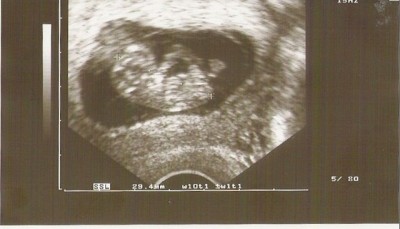

beweiss.

Dateianhänge

Scannen.jpg

So heute war mein Termin habe meinen Mutterpass bekommen,oh man es ist so ein wunderschönes Gefühl Man kann schon beinschen und Ärmchen sehen,und zugelegt habe ich auch ganz schön Am 15.01 habe ich meinen nächsten Termin Ab Morgen bin ich wieder Arbeiten mal gespannt was auf mich zu kommt.Nur habe ein kleines Problem mein Arbeitsvertrag geht bis zum 15.05 habe aber erst am 1.08 ausgezählt steht mir Arbeitslossengeld zu?Obwohl ich hoch schwanger bin ?Muss mich mal erkundigen. :dance: